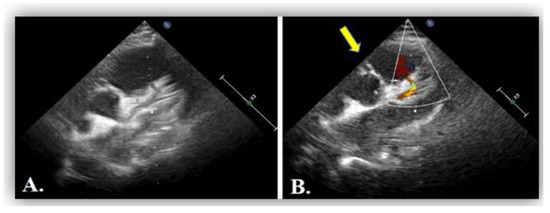

Coronary anomalies, although rare, should be considered when young patients present with angina. Clinical suspicion and multi-modality imaging including coronary angiography and tomographic imaging should be pursued for symptomatic patients such as the one we are presenting with anomalous right coronary artery from the pulmonary artery. She was promptly referred for surgical intervention with re-implantation of the right coronary artery onto the aorta. Full article

Show Figures

Figure 1